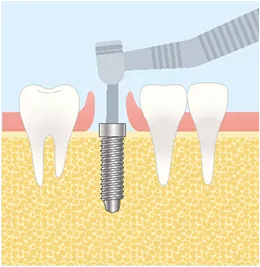

FLOW01

一次オペ

(インプラント埋入)-

STEP3

インプラント埋入

FLOW02

二次オペ

(アバットメントの装着)-